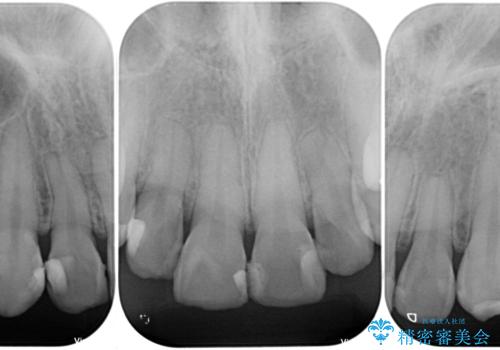

- 前歯の色味が気になるとのことで来院された患者様です。今までに保険のプラスチック(コンポジットレジン)で虫歯の治療をしており経年的な劣化により着色が目立つようになっていました。また歯と歯の隣り合っているところに段差もあり虫歯になっているところもあったため前歯6本のオールセラミッククラウンによる治療を行うこととなりました。

拡大鏡視野下で保険のプラスチック(コンポジットレジン)、虫歯を除去し、オールセラミッククラウンに適した形にしました。